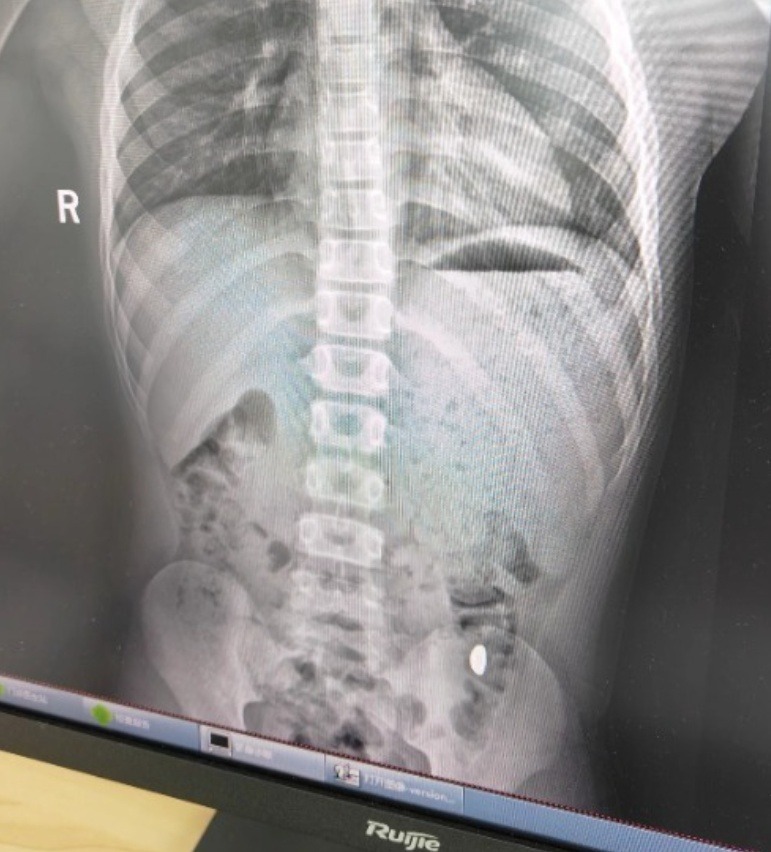

Hồ sơ khám tại Bệnh viện Nhân dân số 5, thành phố Côn Sơn (Tô Châu) ghi nhận bệnh nhi nuốt nhầm khoảng 10 gram vàng, đã đi vệ sinh 2 lần nhưng chưa thấy vàng. Hiện tại không có đau bụng hay nôn ói, chẩn đoán cho thấy còn dị vật trong dạ dày. May mắn là, sau khi thăm khám buổi sáng, ngay buổi chiều hôm đó, vàng đã được thải ra ngoài.

| Ảnh chụp X-quang của cậu bé nghịch ngợm |